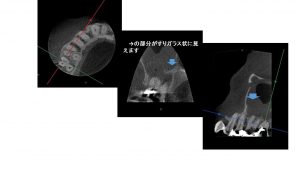

こちらの患者さんの歯の根管治療は適切に行われていなかったので歯性上顎洞炎(蓄膿症)を起こしていることがCT画像で観察されます。上顎洞の面積の半分位上顎洞粘膜が肥厚していてレントゲン上ではすりガラスのような像を見ることが出来ます。

また、根の先に認める膿と上顎洞粘膜が連続している状態がCT像で観察されます。